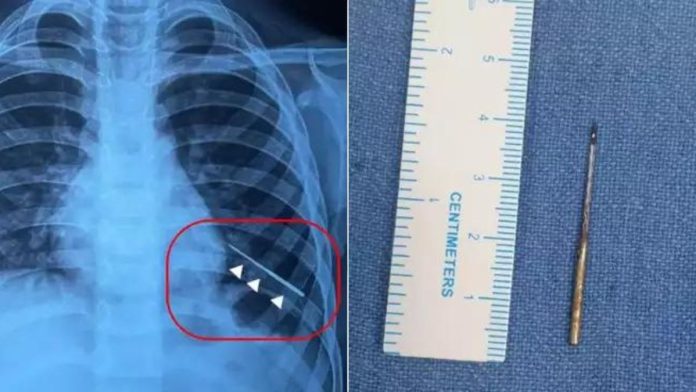

अस्पताल के अनुसार, बच्चे को हेमोप्टाइसिस (खांसी के साथ खून आना) की शिकायत के बाद गंभीर स्थिति में बुधवार को कराया गया। बाल चिकित्सा सर्जरी विभाग के अतिरिक्त प्रोफेसर डॉ. विशेष जैन ने बताया कि रेडियोलॉजिकल जांच से पता चला कि बच्चे के बाएं फेफड़े फेफड़े की गहराई में लगभग 4 इंच का सिलाई मशीन एक सुई फंसी हुई थी। इसका पता चलने पर बच्चे के घरवालों के साथ डॉक्टर भी हैरान रह गए।

डॉक्टरों के अनुसार, फेफड़ें में सुई ऐसी जगह धंसी हुई थी जहां ब्रोंकोस्कोपी उपकरण के लिए बहुत कम जगह थी। ऐसे में एम्स के डॉक्टरों ने देसी जुगाड़ का इस्तेमाल किया। उन्होंने एक दुकान से चुंबक मंगवाई। टीम ने सरलतापूर्वक एक विशेष उपकरण तैयार किया। इसमें चुंबक को एक रबर बैंड और धागे का उपयोग करके सुरक्षित रूप से जोड़ दिया गया था। इसके बाद बड़ी सावधानी से चुंबक की मदद से सुई को बाहर निकला गया।